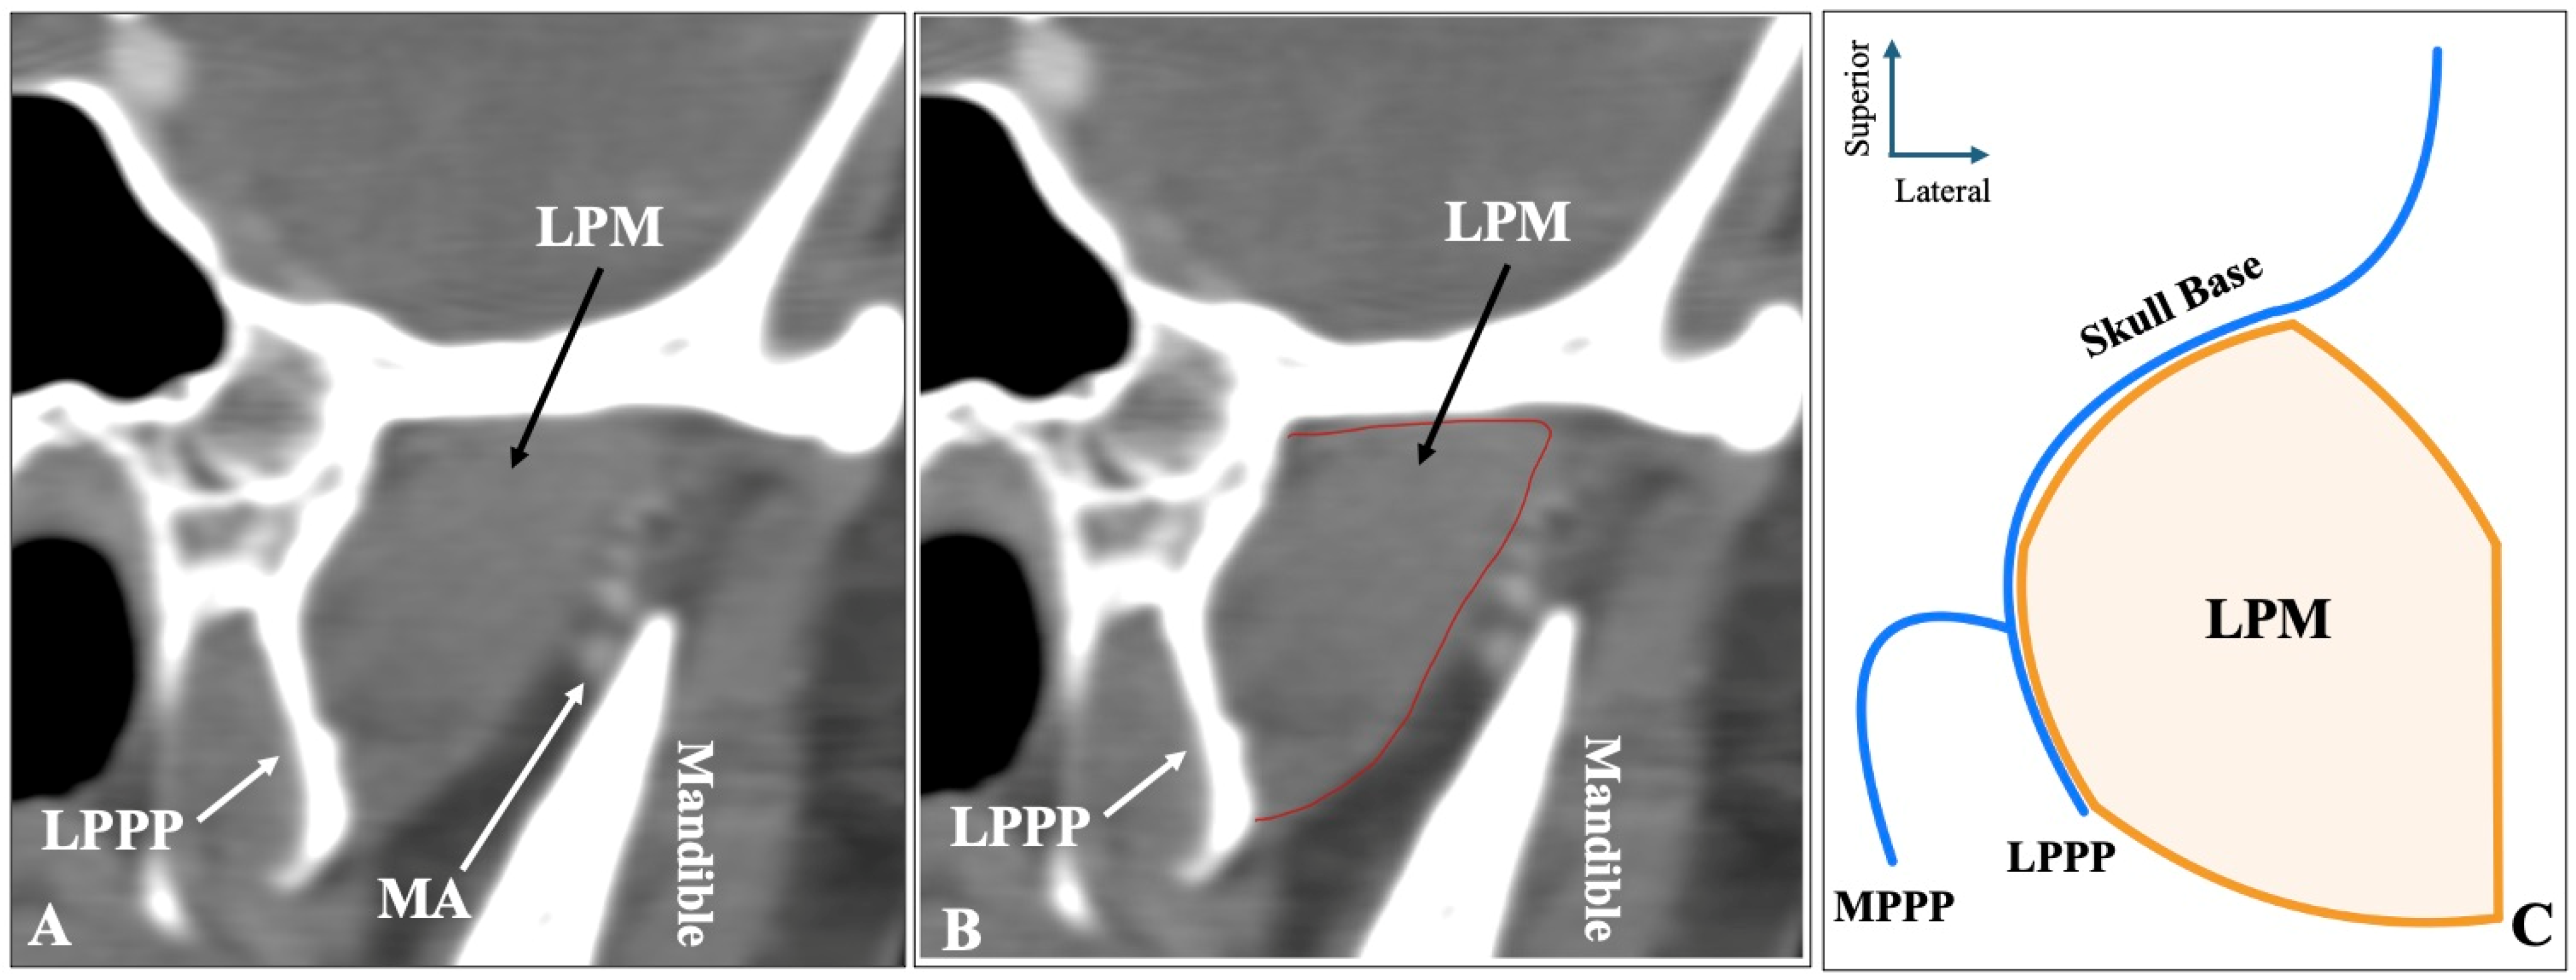

The most common morphology of the muscle was the two-headed configuration (superior-inferior) recorded in sagittal slices, identified in 372 sides (74.4%) (Figure 1). Symmetrical two-headed morphology was noted in 152 patients (60.8%). Out of the 372 sides with two-headed LPM, 230 sides (61.8%) had the MA lateral to the muscle, 122 sides (32.8%) medial to the muscle, and 20 sides (5.4%) through it.

Figure 1.

The two-headed configuration of the lateral pterygoid muscle (LPM) observed in sagittal computed tomography angiography (CTA) slices (A,B) and in schematic representation (C). LPMsh = lateral pterygoid muscle, superior head; LPMih = lateral pterygoid muscle, inferior head; LPPP = lateral pterygoid process plate.